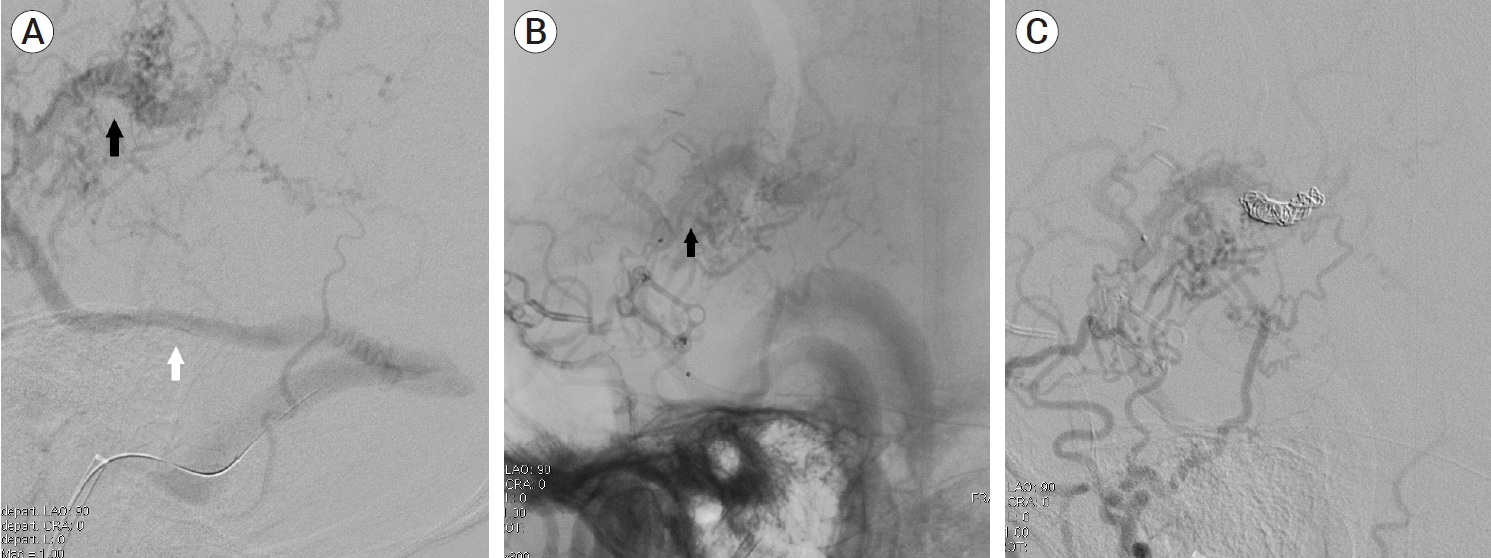

Fig. 2.

(A) Left external carotid artery angiography demonstrating multiple feeders from the middle meningeal artery and superficial temporal artery. Drainage pattern to engorge the superficial middle cerebral vein (black arrow) and vein of Labbe (white arrow) is noted. (B, C) Left internal carotid artery angiography showing additional multiple pial arterial feeders arising from the middle cerebral artery (black arrow).